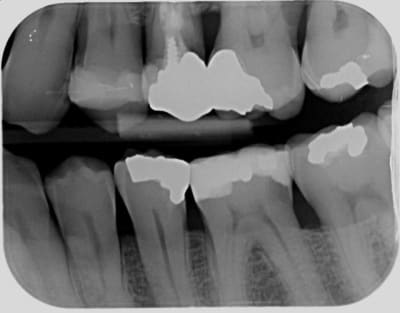

Je compare les btw precedents et tombe sur un hic au niveau de 36 en evolution depuis 2010.

Pour ce que je vois sur les radios, ces soins sont propres, mais pas exceptionnels. Notamment les faces proximales, reconstituées avec des matrices insuffisamment galbées qui produisent un point de contact presque occlusal et qui ne protège pas très bien l'espace inter dentaire en évitant aux aliments de se coincer.

Ceci étant, nous avons tous des patients qui ne passent pas assez les brossettes inter dentaires et déclenchent des caries cervicales incontrôlées.

je m'inquiéterais aussi pour la 25.

face distal de 23 également, y a une petite radio clarté.